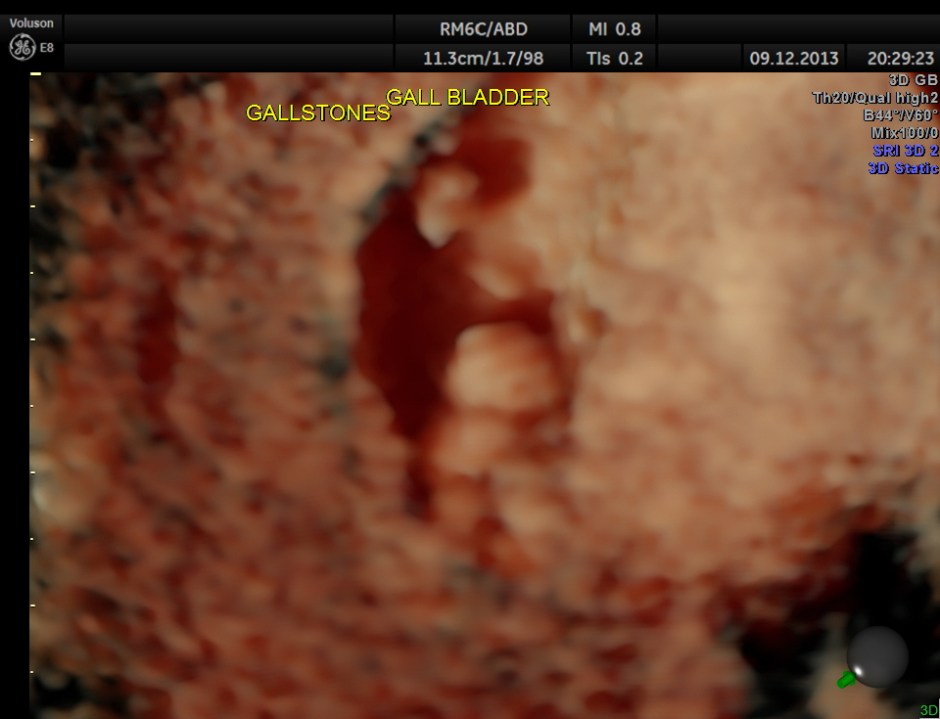

high-definition rendering is given below.

Usually the patient and the surgeon are interested in knowing the number of gallstones . I always have felt that the number would not matter . But is there a difference between 2D , 3D and more advanced high-definition rendering ? Please decide for yourself.